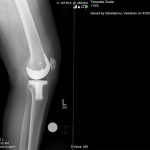

Ο ορθοπεδικός – χειρούργος Βασίλειος Σακελλαρίου στην Αθήνα αντιμετωπίζει επιτυχώς κάθε είδους κακώσεις γόνατος και ισχίου. Παρακάτω παρουσιάζονται πολλές περιπτώσεις κακώσεων που αντιμετωπίστηκαν επιτυχώς από τον χειρούργο – ορθοπεδικό. Δείτε τις αναλυτικά: